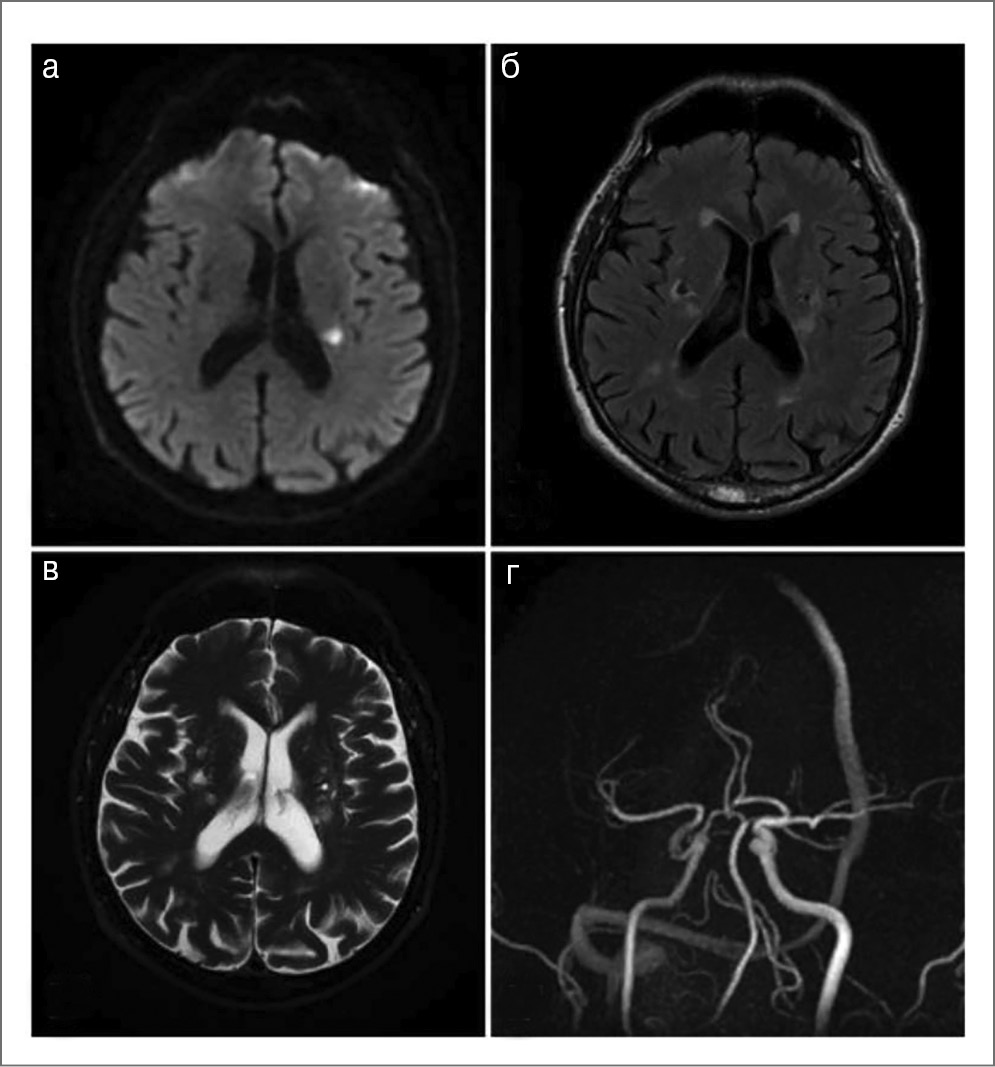

В диагностике лакунарного инсульта ведущее значение имеют МРТ головного мозга с оценкой признаков ЦМА в соответствии с критериями STRIVE [38] и исключение ИКА (рис. 5).

Рис. 5. Клинический пример. Пациент 64 лет, страдающий артериальной гипертензией и сахарным диабетом 2-го типа: а – лакунарный инфаркт в зоне полуовального центра слева (МРТ DWI); б – лакуны в глубинных отделах обоих полушарий, гиперинтенсивность белого вещества (МРТ FLAIR); в – расширение глубинных периваскулярных пространств (T2); г – нормальный результат бесконтрастной МРА. Все это соответствует проявлениям гипертензионной микроангиопатии.